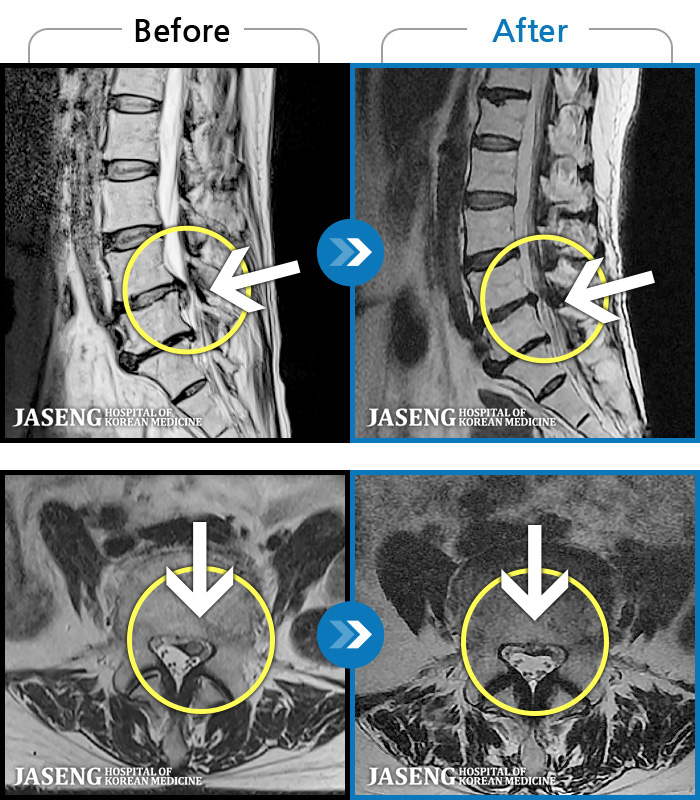

1,237 MRI ũ ʸ Ȯϼ.

1,237